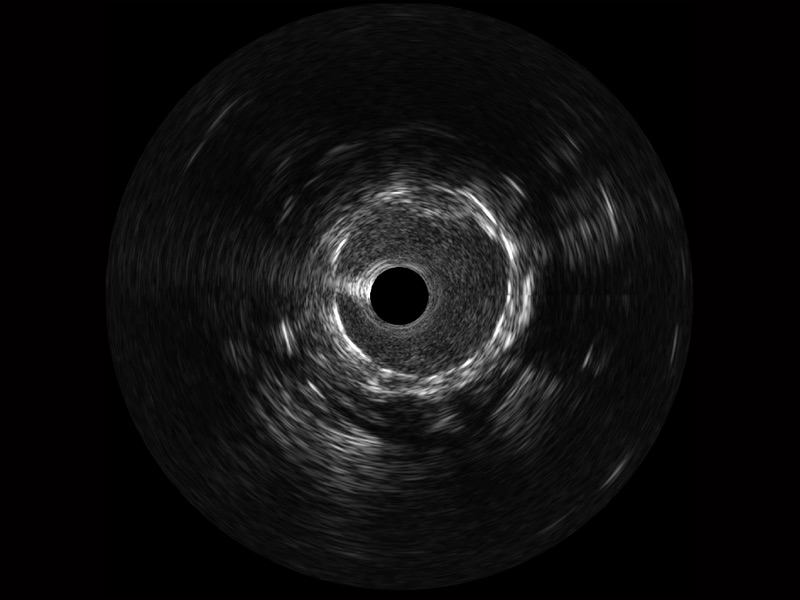

血管内超声(IVUS) 通过对病变程度、性质和累及范围的精确判断,可帮助选择治疗策略和方法,指导介入治疗过程,能够降低主要不良心血管事件,改善预后,在复杂病变介入治疗中用于指导支架置入的优势更为明显。血管内超声(IVUS)已成为精准心血管介入治疗的“金标准”。

16877太阳集团超宽频成像技术覆盖20-80MHz1或20-90MHz2频率范围, 提供优异的分辨力同时也保证充足的穿透深度

对比传统IVUS导管成像,16877太阳集团宽频IVUS图像的近场支架梁显影更细腻,远场中膜外血管仍清晰可辨,兼顾远中近,兼顾分辨力与穿透深度